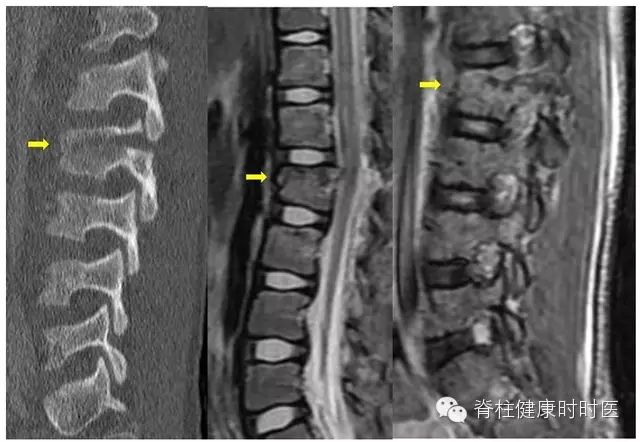

100例患者(205处骨折)MRI检查提示骨髓水肿。对骨折进行分类后再分析,骨折类型与骨髓水肿密切相关,92例患者的188处压缩骨折,与骨髓水肿及程度相关。齿状突骨折 42 例,基本没有骨髓水肿(图 1)。12 例经椎间和 / 或邻近终板的骨折,亦无骨髓水肿(图 2)。10 例强直性脊柱炎患者,经椎间 - 终板或椎体的骨折,骨髓水肿有限或没有(图 3)。6 例 Chance 骨折,均无骨髓水肿(图 4)。

图 4 Chance 骨折。左图:L2 Chance 骨折并略分离。中图:MRI 未见骨髓水肿。右图:无 T2 相异常信号。箭头表示 L2 骨折处。